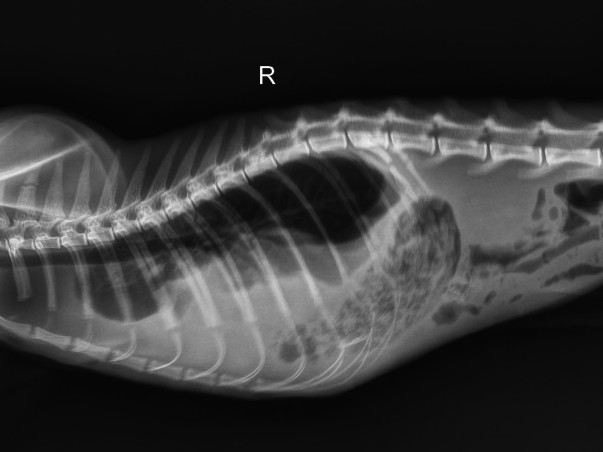

After emergency examination, blood tests, X-rays, ultrasound scans, and further imaging at Cessna Lifeline Veterinary Hospital, the doctors have confirmed that he is suffering from a diaphragmatic hernia.

A diaphragmatic hernia is a life-threatening condition where the muscle separating the chest and abdomen tears, usually due to trauma such as a fall or road accident. Because of this tear, abdominal organs move into the chest cavity and compress the lungs, making breathing extremely difficult.